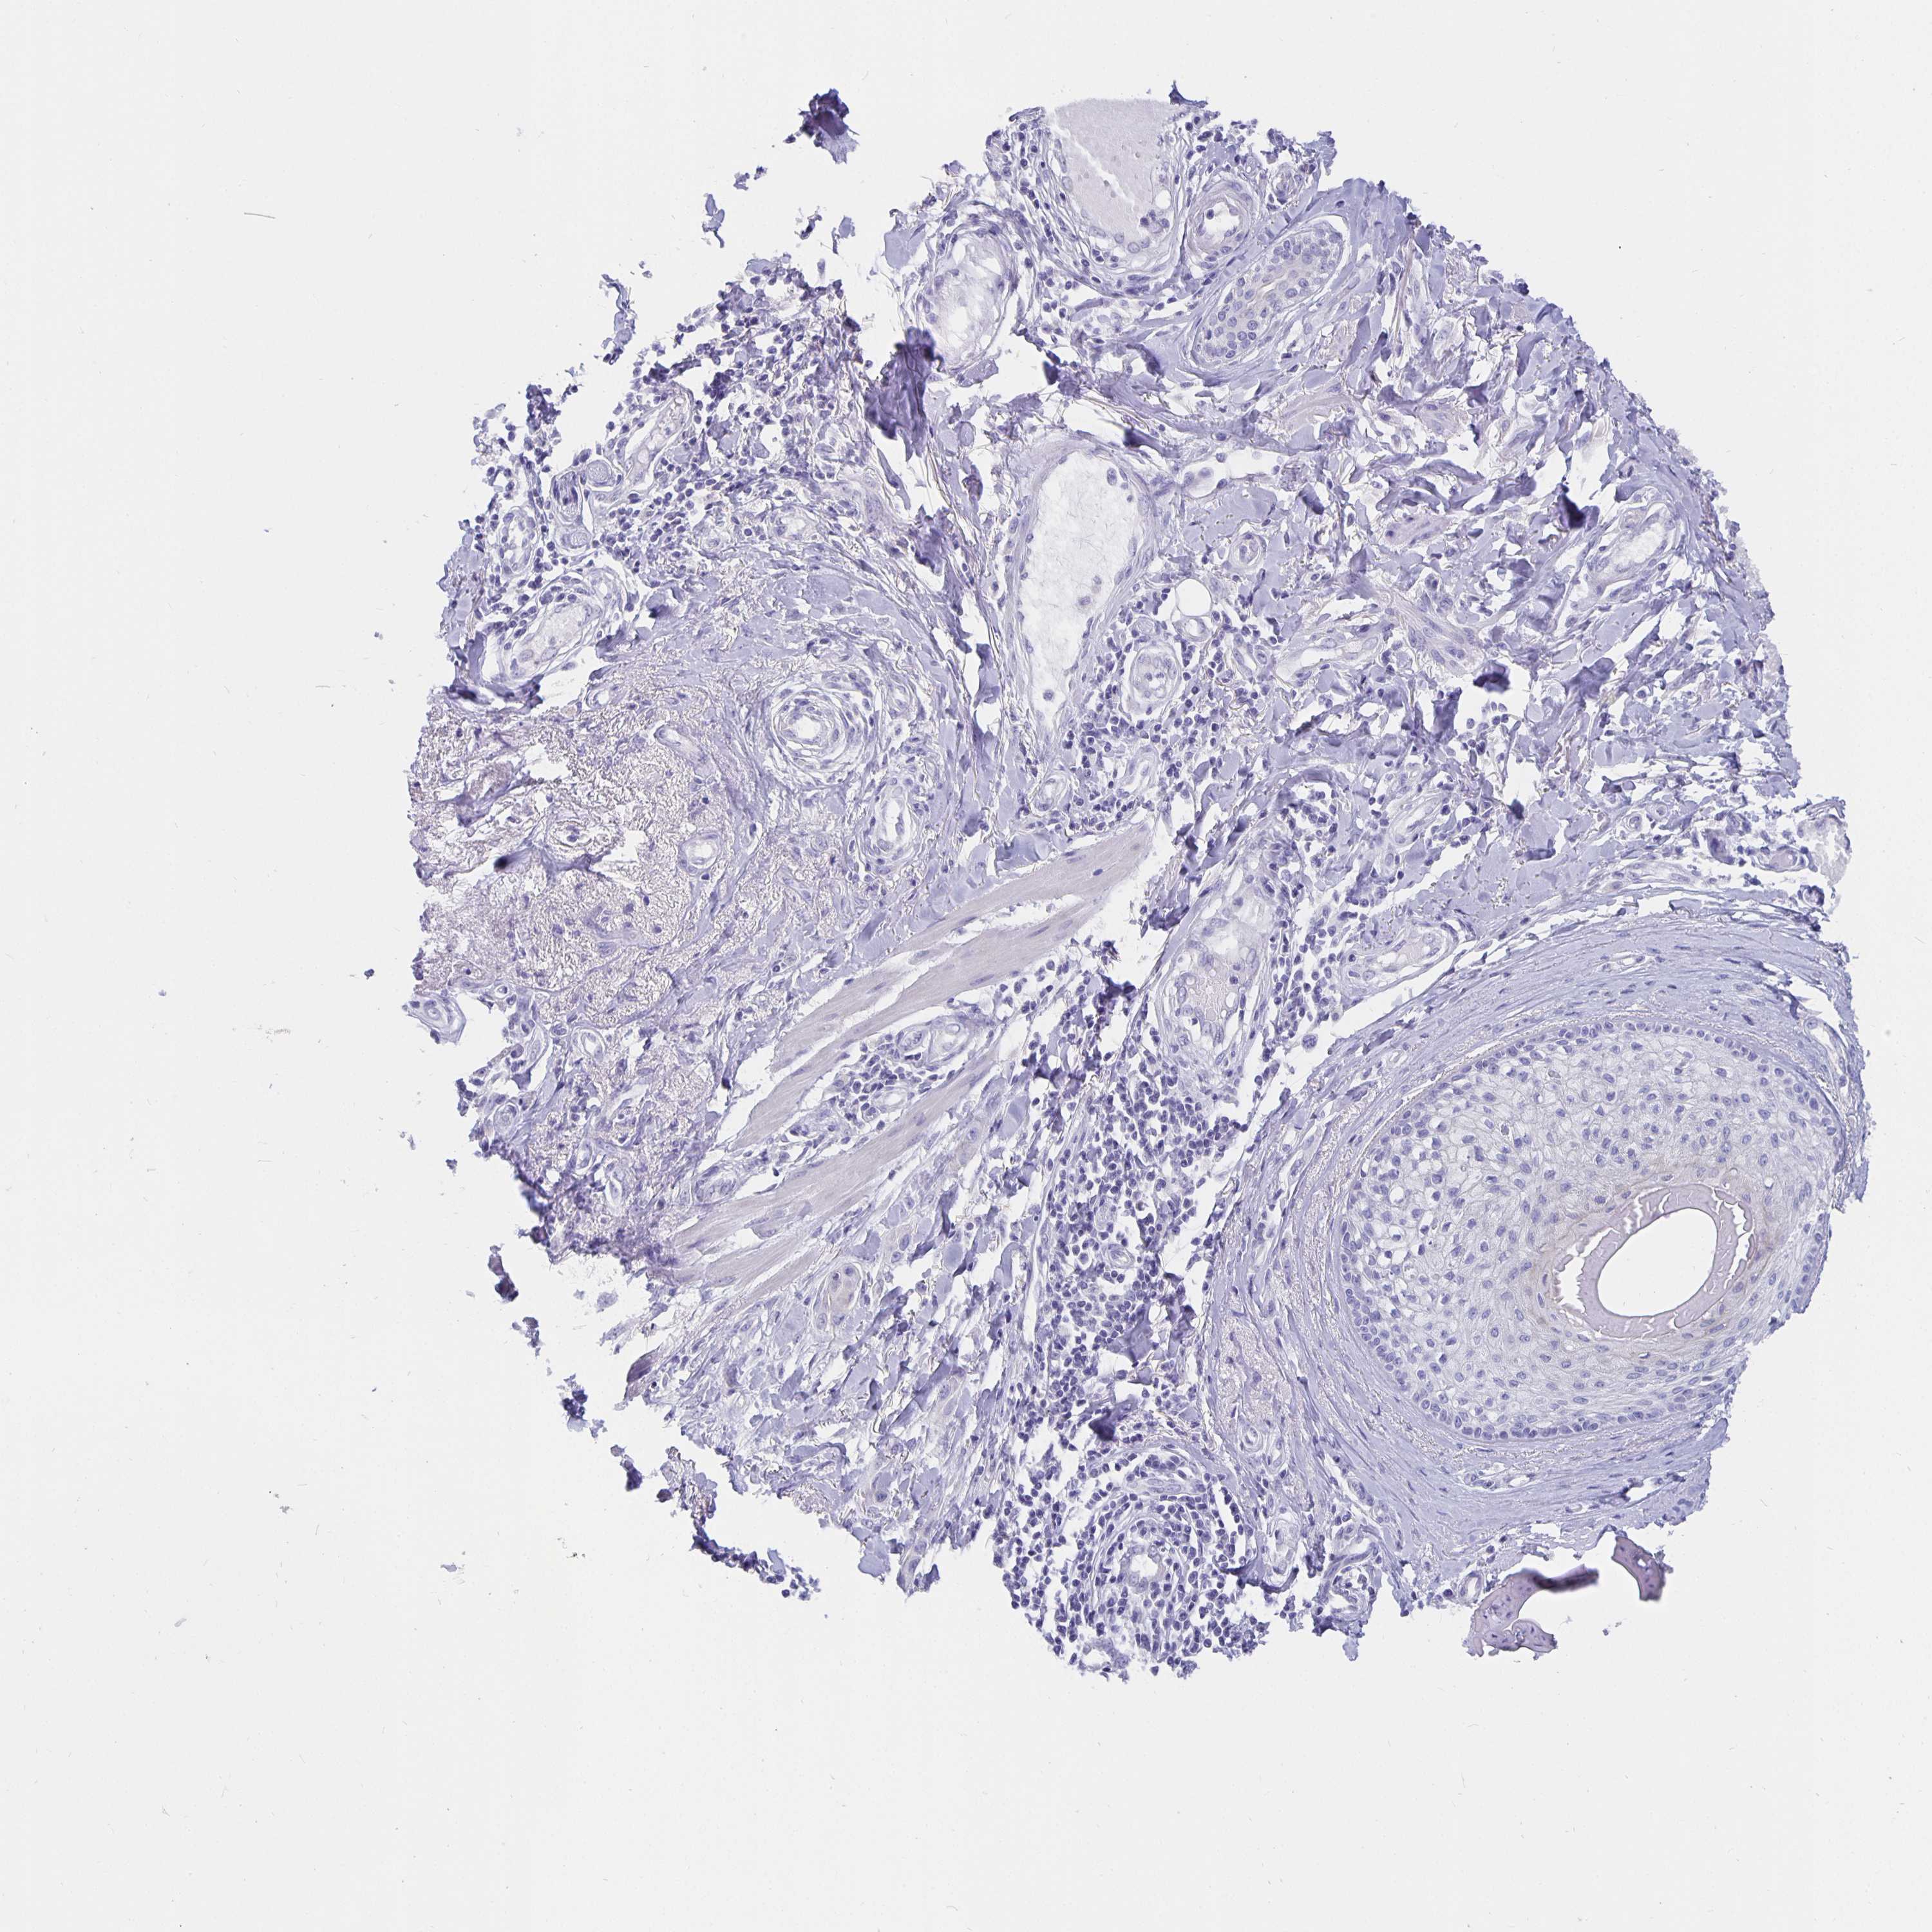

SKIN CANCER - Protein expressioni

A mouse-over function shows sample information and annotation data. Click on an image to view it in a full screen mode. Samples can be filtered based on level of antibody staining by selecting one or several of the following categories: high, medium, low and not detected. The assay and annotation is described here.

Each image is clickable and will lead to virtual microscopy that enables deeper exploration of all samples and also displays staining intensity scores, fraction scores and subcellular localization as well as patient and tissue information for each sample.

Antibody HPA028521

Antibody HPA029274

Antibody HPA030240

Staining

High

Medium

Low

Not detected

Intensity

Strong

Moderate

Weak

Negative

Quantity

>75%

75%-25%

<25%

None

Location

Nuclear

Cytoplasmic/membranous

Cytoplasmic/membranous,nuclear

Basal cell carcinoma

Squamous cell carcinoma, NOS